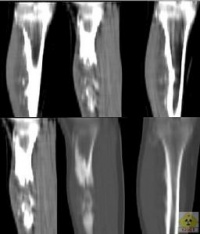

3.CT检查:能清晰的显示出肿瘤与受累骨皮质和松质骨相连,软骨帽部分呈软组织密度,有时可见不规则的钙化及骨化。

4.MRI检查:骨性部分的信号与相邻干骺端松质骨的信号相同,软骨帽在T1加权像上呈低信号,T2加权像上呈高信号。MRI检查可以明确软骨帽的厚度,如超过25mm者应考虑有恶变可能。